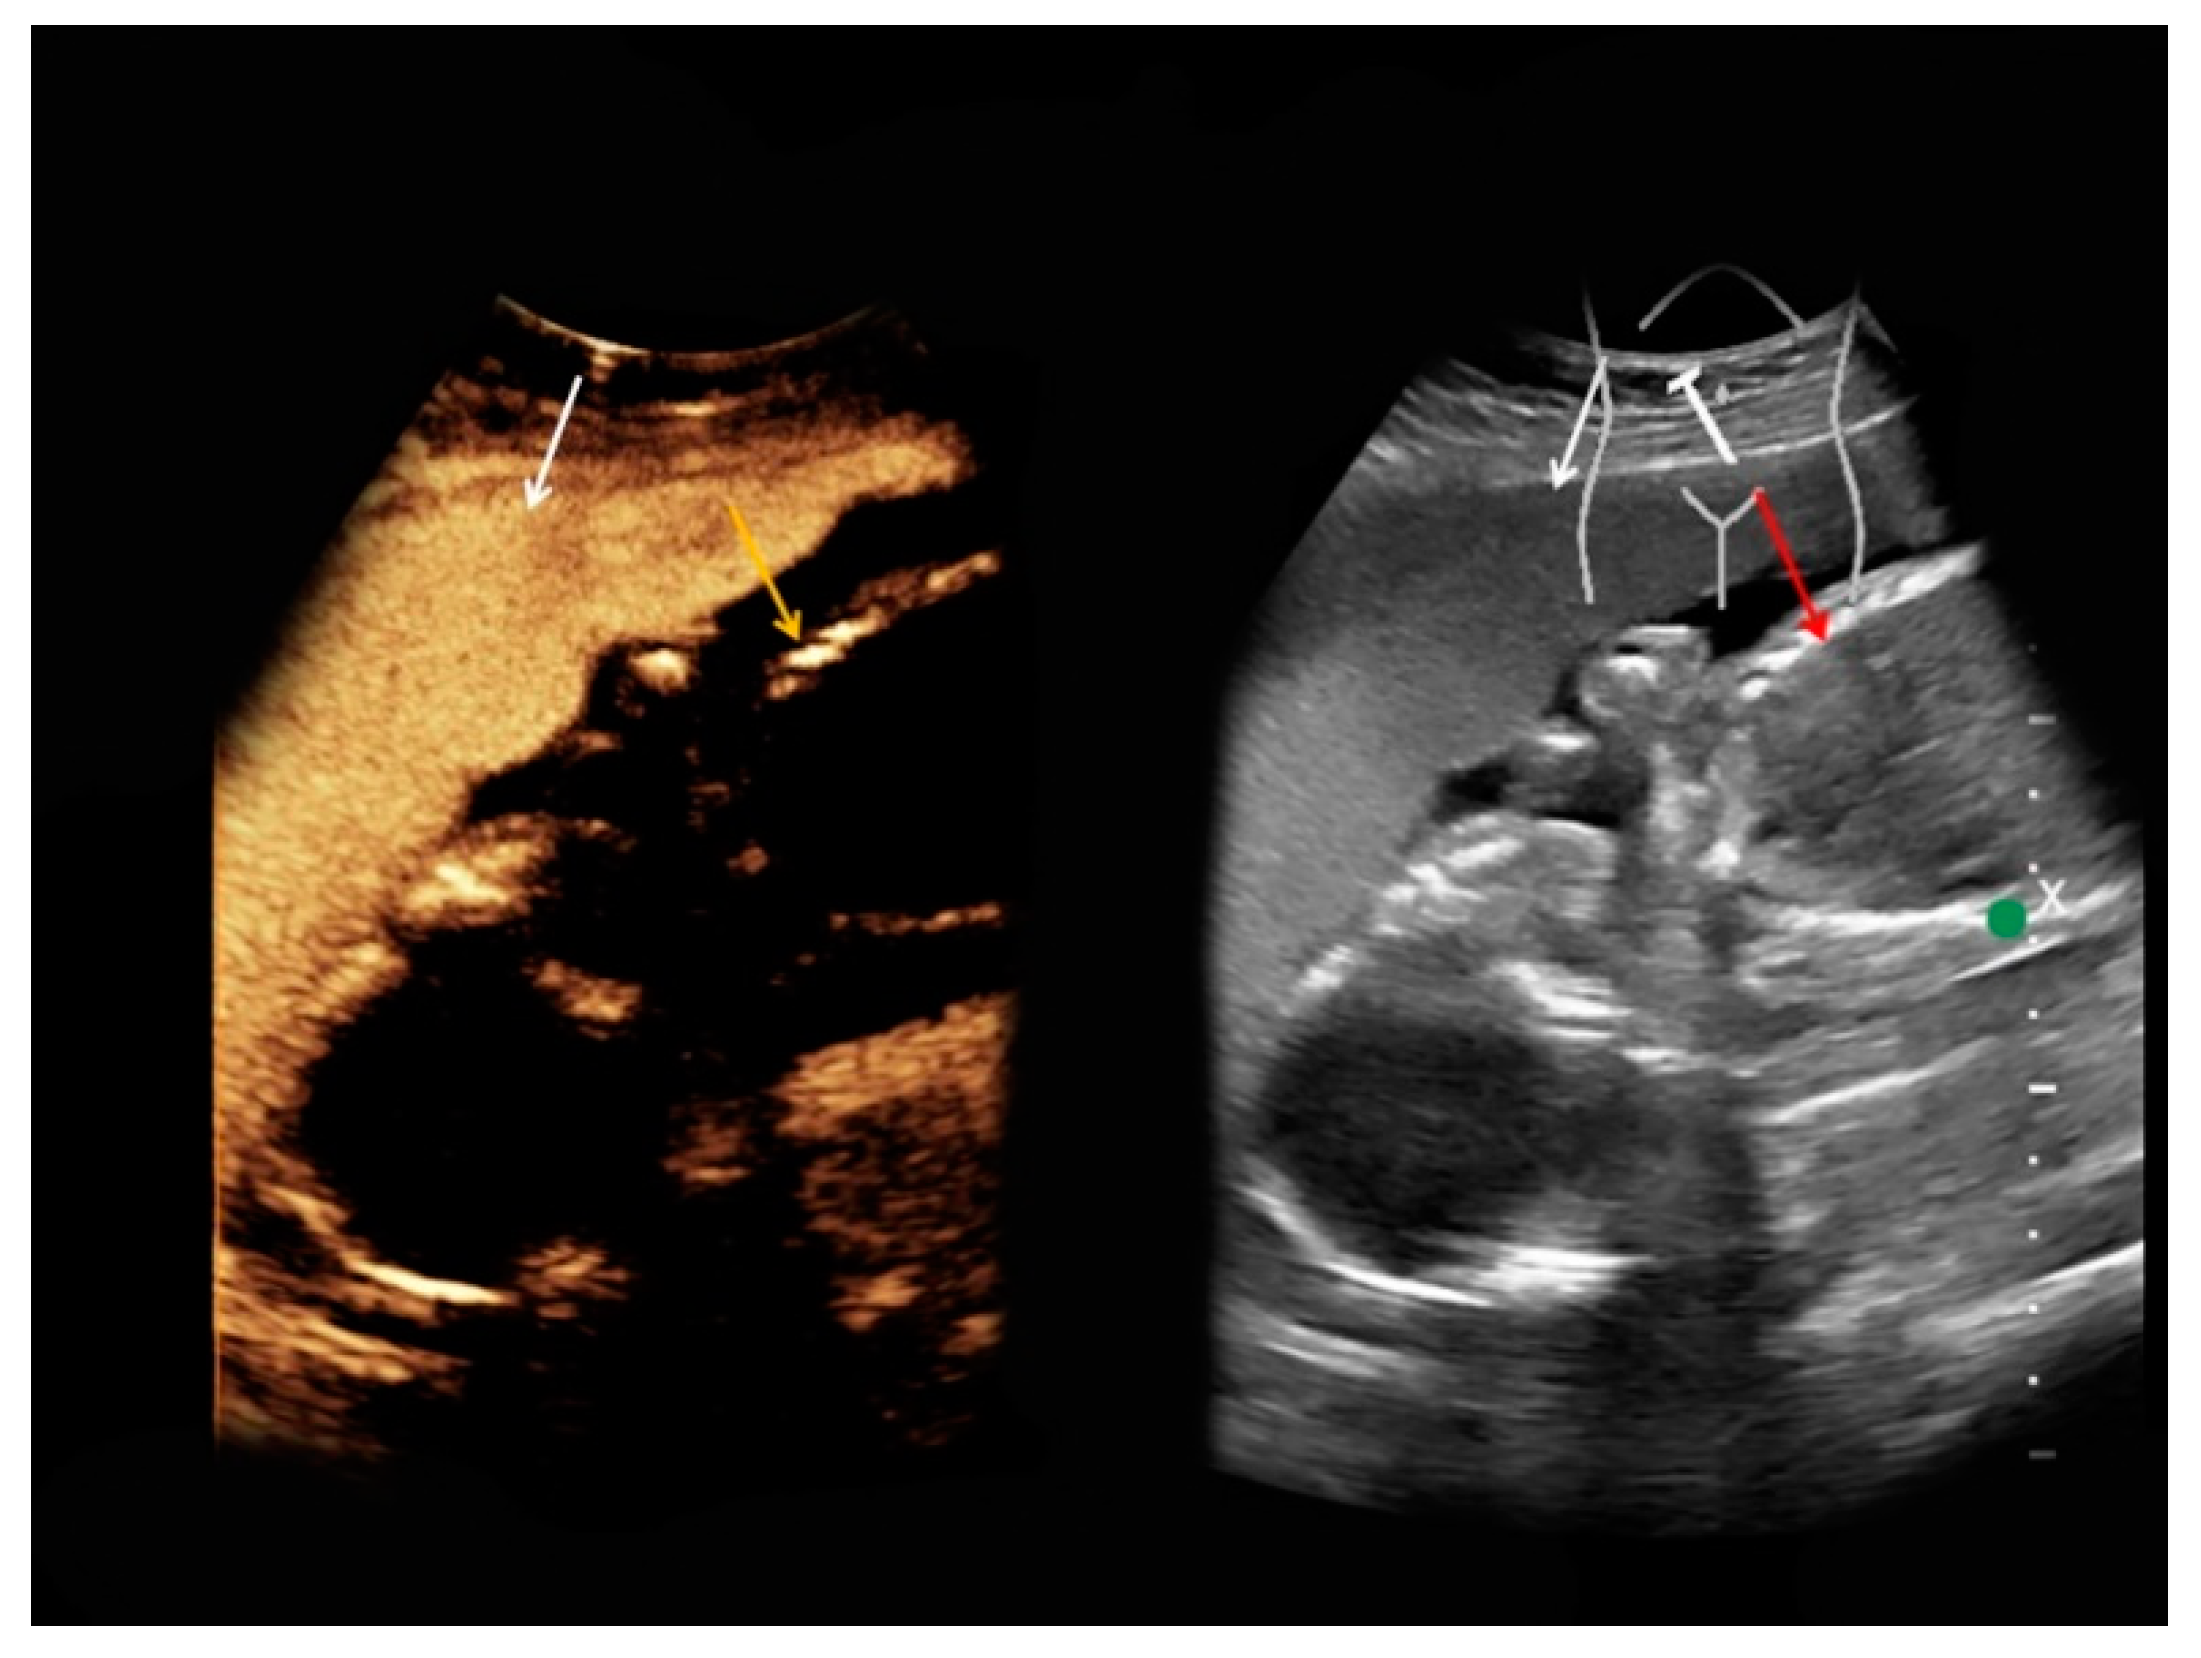

| #1 | 30 | 27 | Renal angiomyolipoma | B-mode: hypoechoic, 14 cm Doppler: no hypervascularization CEUS: rapid early contrast enhancement, slight late wash-out | T1-hypointense, T2-hypointense, restricted diffusion |

| #2 | 37 | 21 | Pyelonephritis, ruled out the presence of an abscess | B-mode: no abnormalities Doppler: no abnormalities CEUS: homogeneous contrast enhancement, no abscess | homogeneous, restricted diffusion, perirenal fluid collections |

| #3 | 34 | 25 | Necrotic uterine fibroid | B-mode: inhomogeneous, hypo-/hyperechoic, 15 cm Doppler: no hypervascularization CEUS: slight contrast enhancement | inhomogeneous, predominantly T1-hypointense, T2-hypointense |

| #4 | 33 | 17 | Gallbladder polyp | B-mode: hyperechoic, 0.6 cm Doppler: no hypervascularization CEUS: homogeneous, late contrast enhancement | - |

| #5 | 34 | 14 | Superior mesenteric vein thrombosis | B-mode: no abnormalities Doppler: no Doppler signal in the superior mesenteric vein CEUS: only slightly marginal microbubble distribution in the superior mesenteric vein | small superior mesenteric vein thrombosis |